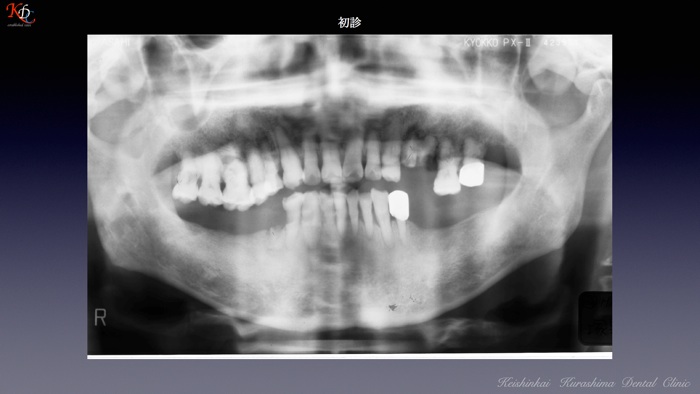

治 療例 1